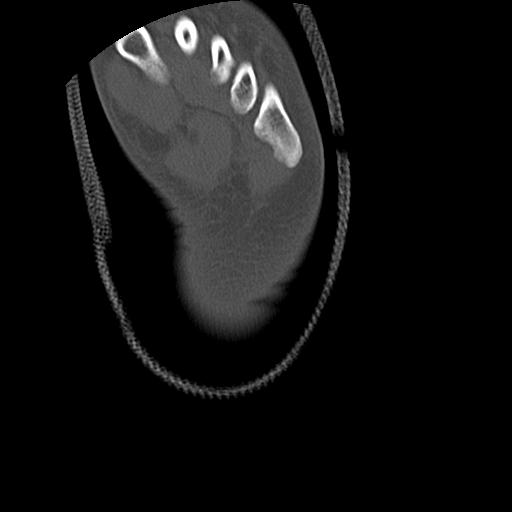

102803 1/12(キウスなし) 1/27 左下腿 4R 30歳女性 左脛骨軸内釘